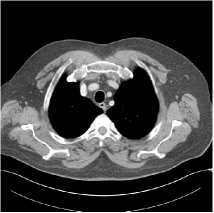

Refer to caption WavResNet [11]Refer to caption WavResNet [11]Refer to caption WavResNet [11]Refer to caption Momentum-Net (SimpleCNN)Refer to caption Momentum-Net (SimpleCNN)Refer to caption Momentum-Net (SimpleCNN)Refer to caption Momentum-Net (SimpleCNN-RSN)Refer to caption Momentum-Net (SimpleCNN-RSN)Refer to caption Momentum-Net (SimpleCNN-RSN)Refer to caption Momentum-Net (Dn-RSN)Refer to caption Momentum-Net (Dn-RSN)Refer to caption Momentum-Net (Dn-RSN)Refer to caption ReferenceRefer to caption ReferenceRefer to caption Reference

Fig. 3: Three examples (from top to bottom) of the reconstructed testing images using Momentum-Net with SimpleCNN (the second column), with SimpleCNN-RSN (the third column), and with Dn-RSN (the fourth column). The compared WavResNet denoised images are shown in the first column, and the reference images are in the fifth column. See their FBP images in Fig. 4.

Fig. 2 shows that the proposed Momentum-Net with SimpleCNN decreases RMSE dramatically in the first 30 layers, and tends to converge in 50 layers. The Momentum-Net reduces the mean RMSE value by 4.5 HU and gives smaller standard deviations in RMSE, compared to WavResNet, as reported in Table 1. This implies that the proposed Momentum-Net with SimpleCNN can improve both the accuracy and stability of low-dose CT image reconstruction than a state-of-the-art image denoising deep NN, WavResNet. The proposed Momentum-Net with SimpleCNN better removes noise and streak artifacts than WavResNet. It also provides clearer reconstructions of some details; see, in Fig. 3, the boundaries shown in the zoomed region at the top-right corner in the first example, the arrow pointed structures in zoomed areas of the second example, and the arrow pointed tissues in the left zoomed region in the third example.

We show the reconstructed examples by Momentum-Net with SimpleCNN-RSN and Dn-RSN in the third and fourth columns of Fig. 3 respectively. Comparing the first three and the last columns in Fig. 3, we observe that Momentum-Net with SimpleCNN-RSN provides generally noisier reconstructions than WavResNet and Momentum-Net with SimpleCNN. However, Momentum-Net with SimpleCNN-RSN sometimes can provide clearer details than WavResNet. For example, in the right zoomed box of the second example, Momentum-Net with SimpleCNN-RSN shows better reconstruction quality for the arrow pointed structures than WavResNet, and in the left zoomed box in the third row, the former gives clearer small tissues marked by red arrows than the latter. Table 1 reports that Momentum-Net with SimpleCNN-RSN is approximately 2.9 RMSE (HU) higher than WavResNet, while it has smaller standard deviations. This implies that Momentum-Net with SimpleCNN-RSN is more stable than WavResNet, although it may not provide better image qualities. Momentum-Net with Dn-RSN, however, provides the worst visual and numerical results among the compared four methods in this paper.